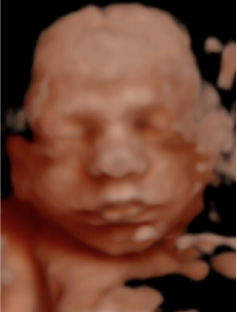

Experimenta la última tecnología hiperrealista 8K, una imagen increíblemente detallada y realista de los rasgos de tu bebé, con una textura y definición que te sorprenderán.

El mayor realismo sin artificios

Respetamos la ecografía original.